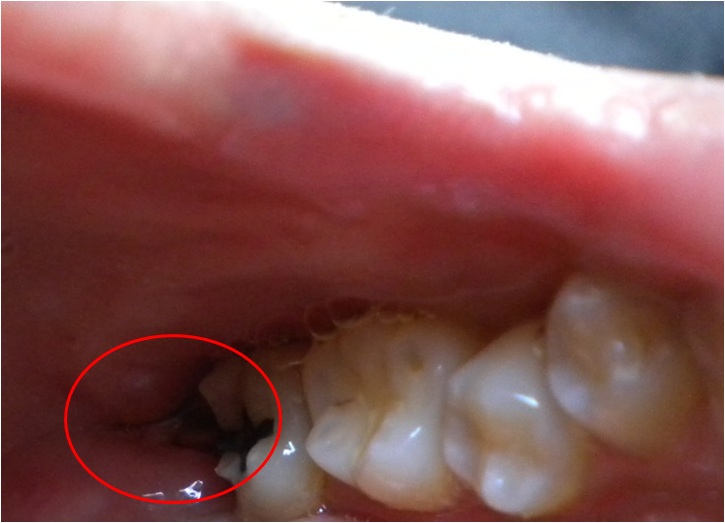

Bdfore After 抜いた歯

分かりにくいが、親知らず 親知らずがなくなって、 骨もいっしょに

がうっすら見える。 歯ぐきだけに。 ついてきた・・・。